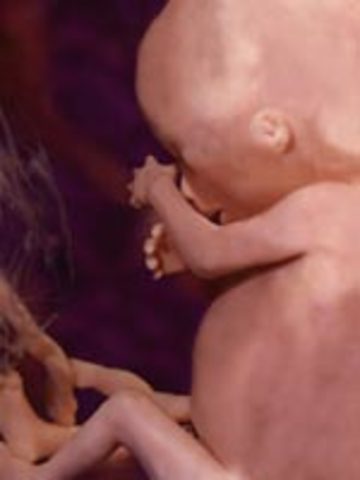

• Week 12

Week 12

Fetus' face is starting to look like a human baby. Nails start appearing. Pancreas begins to function and fetus can hiccup and suck thumb